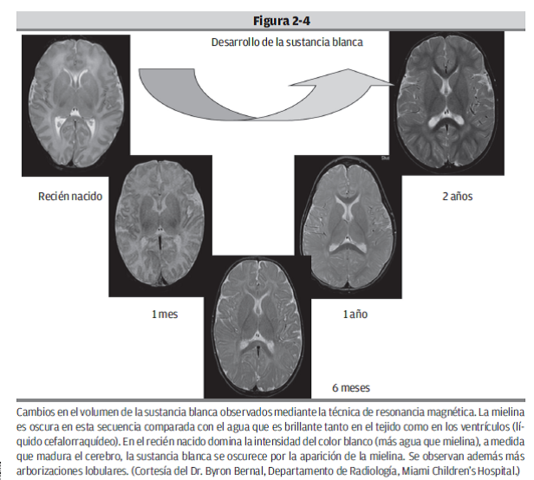

En el proceso de mielinización las células gliales cubren los axones con una capa de mielina, que está hecha de proteínas y lípidos, que hace que la conducción eléctrica del axón sea más rápida y con un menor consumo energético. inicia unos tres meses después de la fecundación, y ocurre progresivamente en tiempos diferentes de acuerdo a la región del desarrollo del sistema nervioso. La última área en mielinizarse es la zona prefrontal.

Otro de los aspectos que suceden durante esta etapa es el proceso de mielinización el cual va en paralelo con el desarrollo cognitivo en el niño. La complejización de las conexiones nerviosas en la corteza cerebral y su mielinización parecen correlacionarse con el desarrollo de conductas progresivamente más elaboradas (Bjorklund y Harnishfeger, 1990, Lecours,1975).

AL igual la maduración de las vías nerviosas (sust, blanca) que se relaciona con la mem. de trabajo y la hab. visoespacial

Algunos de los indicadores de maduración son: al cambio estructural de las neuronas con incremento de los axones y de las arborizaciones dendríticas. A medida que el cerebro se desarrolla se observa un número mayor de conexiones nerviosas con cambios en el nivel de espesor de las capas de la corteza cerebral. Otro indicador es el incremento de la mielinización de los axones que permite una conducción mucho más rápida del impulso nervioso, además del aumento del volumen cerebral.

La relación entre el volumen de sustancia blanca (vías nerviosas) y el volumen de sustancia gris (cuerpos neuronales) cambia con la edad del individuo. La diferencia entre el cerebro de un niño y el de un adolescente está en el mayor número de conexiones nerviosas en el cerebro de este último. El porcentaje incrementado de sustancia blanca con relación a la sustancia gris es entonces un índice de maduración cerebral asociado a un mejor desempeño cognitivo.